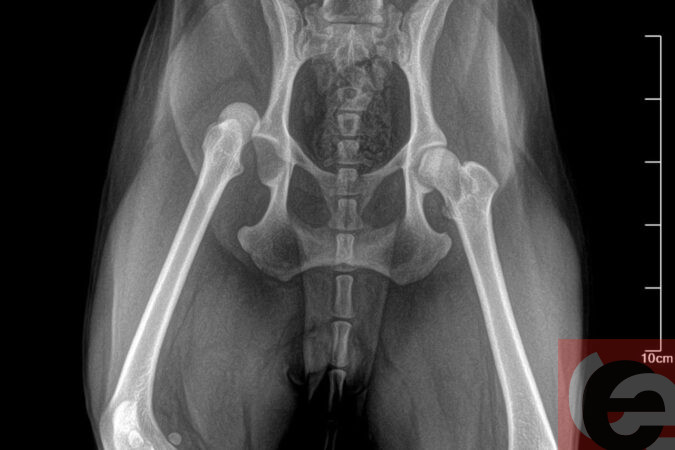

— В ветклинике мне сказали, что нарушилось кровообращение в лапе, поэтому Ника не может самостоятельно ходить. Хотя когда конечности «затекают», это быстро проходит. На следующий день я вновь повела Нику в клинику. Хирург сделал рентген и поставил диагноз — «вывих тазобедренного сустава», — поделилась обеспокоенная сибирячка.